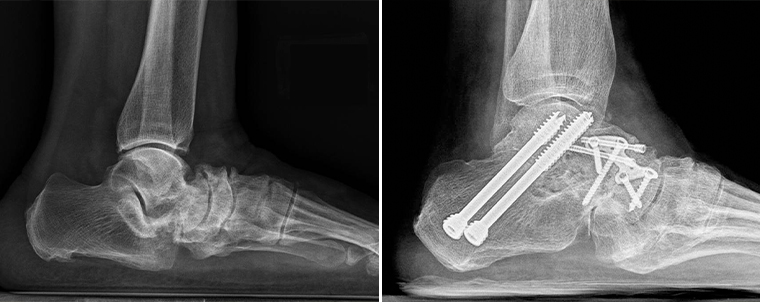

▲患者術前術後的對比圖。(圖/台北慈濟醫院提供)

關於手術的治療方式,王禎麒說明,會將壞死的骨頭移除後,把其他骨頭復位,再取自體髂骨或是以大體老師捐贈的骨頭補在病灶處,加上鋼釘、鋼板讓骨頭更有支撐性,藉由這樣的「關節融合手術」將足踝骨骼融合固定。手術成功率約9成且幾乎不會復發,術後待骨頭品質穩定,須搭配助行器復健,訓練肌力、關節活動度。而相關手術成果也指導骨科年輕醫師發表在2022年的國際知名學術期刊。